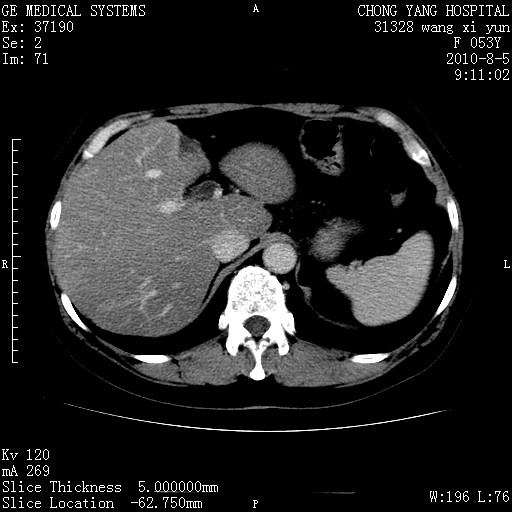

标题: CT28214:F41Y 血尿二十天,建议盆腔平扫加增强。

1)考虑肝左叶胆管细胞癌。2)脂肪肝。

支持胆管细胞ca。